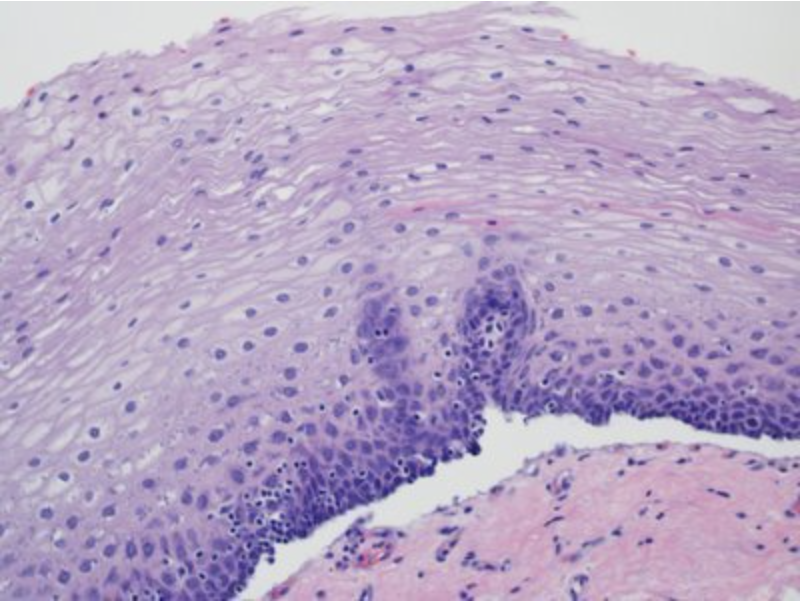

In this image, identify the layer of cells that are involved in renewal of mature epithelial cells!

Epithelial tissues are relatively labile structures whose cells are renewed continuously by mitotic activity and stem cell populations. The rate of renewal varies widely; it can be fast in tissues such as the intestinal epithelium, which is replaced every week. In stratified epithelial tissue such this squamous epithelium of the esophagus, stem cells and mitosis occur only within the basal layer in conact with the basal lamina.